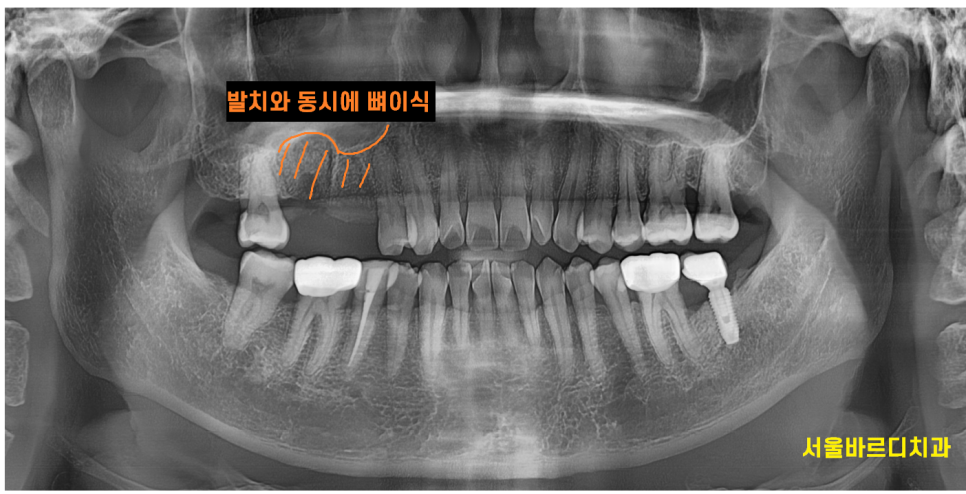

x-ray를 통하여 검사를 해보니

잇몸뼈가 전반적으로 내려가있습니다.

특히나 윗니 양쪽 어금니 부분이 많이 내려가 있으며

오른쪽 윗니 어금니 2개 상태가 많이 안좋습니다.

뿌리쪽에 고름이 있어서

잇몸뼈가 많이 녹았는지 주변보다 까맣게 보입니다.

230329

뼈가 약한 윗니 어금니라...

발치와 동시에 1차 뼈이식을 진행하였습니다.